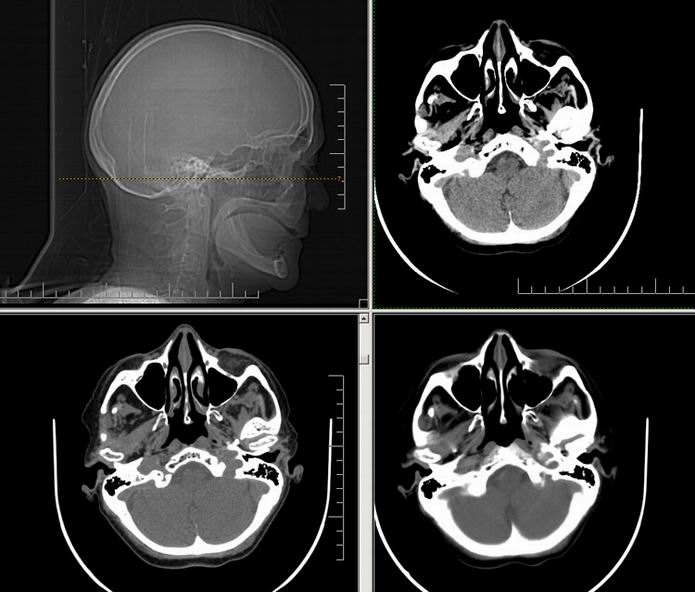

Est ce que qqun a des coupes axiales de crâne pour m'aider à réviser mon anatomie. Merci

Pour compléter tes révisions, Poupette vient de nous faire parvenir ces planches bien utiles: Planches de coupes axiales cérébrales, dans la rubrique COURS / ANATOMIE